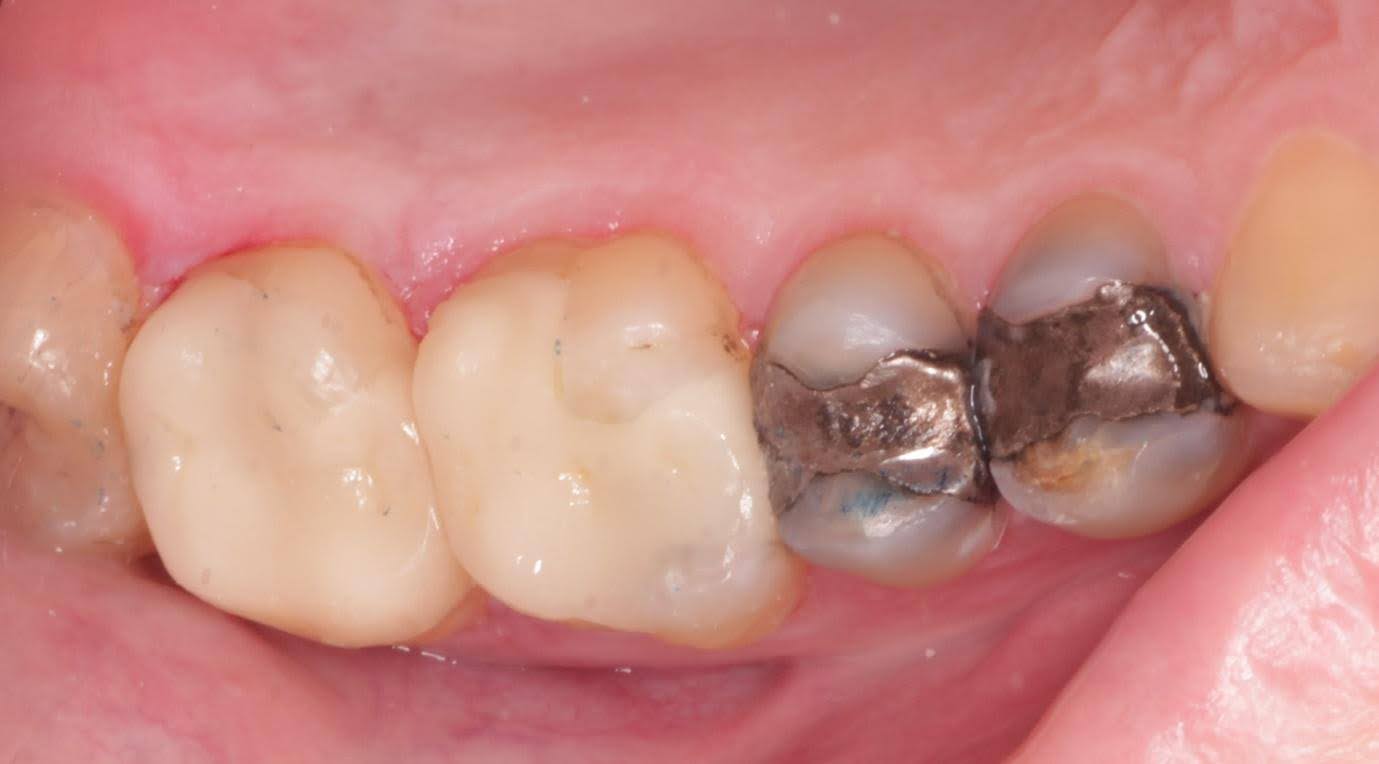

Sequential replacement of failing mercury fillings with porcelain restorations, whilst keeping as much tooth structure intact as possible.